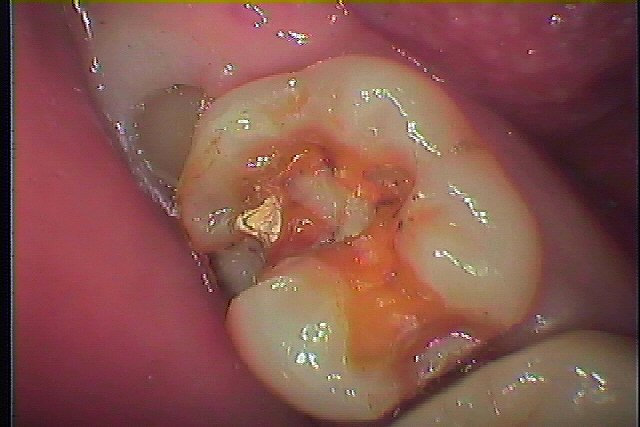

虫歯治療からのセラミックによる審美治療 本来の歯を求めて|お知らせ |広島市安佐南区の歯科医院 虫歯治療からのセラミックによる審美治療 本来の歯を求めて トップ お知らせ・ブログ お知らせ 虫歯治療からのセラミックによる審美治療 本来の歯を求めて 虫歯治療からのセラミックによる審美治療 本来の歯を求めて 右下7番の虫歯治療をおこなっていきます この銀歯をはずしていきます 銀歯をはずしたところになります 中はむし歯になっていました 虫歯を神経に気を付けながら除去していきました CR樹脂にて覆罩を行っています 型取りを行いセレックセラミックにて修復しています このように本来の歯のようにきれいに仕上がりました Web診療予約 初めての方へ 選ばれ続ける理由 院内設備について 歯が痛いしみる一般歯科 歯がぐらぐらする歯周病 健康な歯を保ちたい予防歯科 子供の虫歯予防をしたい小児歯科 銀歯をセラミックに審美歯科 白い歯を目指しませんか?ホワイトニング 矯正専門医がいるので安心矯正歯科 抜けた歯を補いたいインプラント・入れ歯 医院案内 スタッフ紹介 メリィハウス歯科クリニックオフィシャルホームページ ラベンダー歯科クリニックオフィシャルホームページ お知らせ・ブログ ホーム 診療科目 一般歯科 歯周病治療 予防治療 小児歯科 審美治療 ホワイトニング 矯正歯科 入れ歯・インプラント マウスピース矯正 初めての方へ 院長・スタッフ 設備紹介 医院案内・アクセス メニューを閉じる